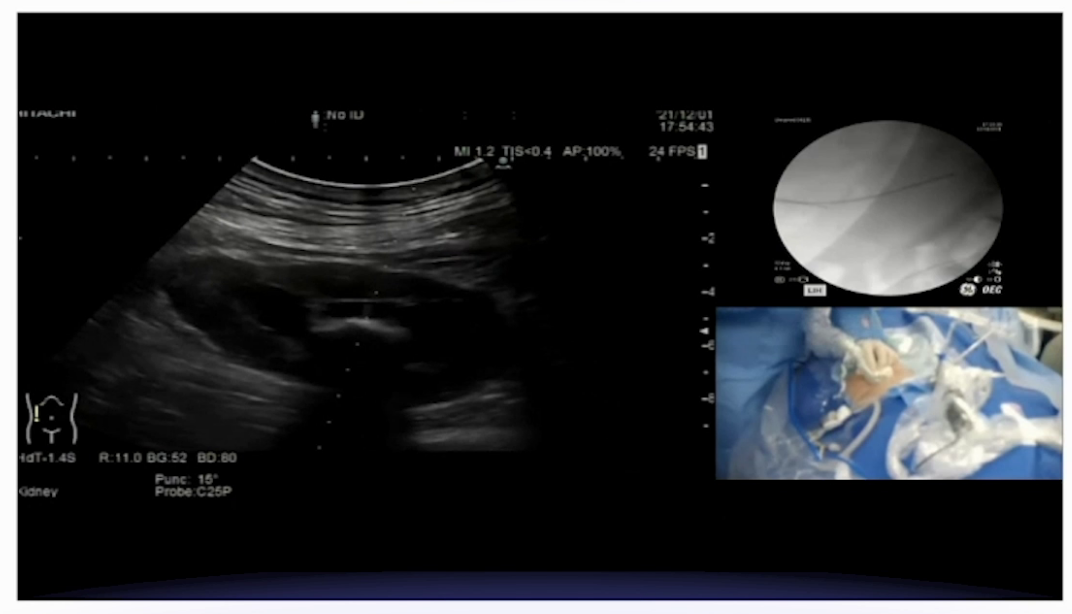

(3)2周后行右侧PCNL,取出结石

2周后,鉴于患者结石负荷大,行B超引导下经皮肾镜取石术。该结石为X线及CT阴性结石,成功穿刺右肾上盏后,打造影剂显示集合系统有明显充盈缺损,结石表面黄褐色。使用气压弹道轻易击碎结石,并通过负压吸引取出。

本例患者诊疗的关键难点在于,其一是术前影像学评估存在偏差,CT虽为结石检查的“金标准”,但本例中未能准确反映结石实际大小,需警惕特殊病史患者的检查局限性;其二是结石处理难度大,该类粘合剂成分结石质地坚硬,软镜下激光碎石难以奏效,最终通过经皮肾镜直接击碎取出,提示特殊成分结石需针对性选择手术方式。